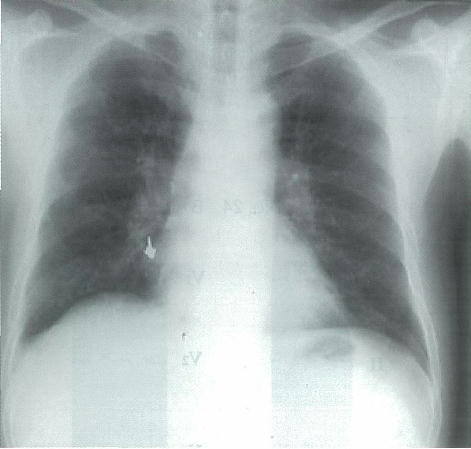

65歳の男性。咳嗽を主訴に来院した。体温 36.6℃。呼吸数 16/分。脈拍 64/分,整。血圧 126/74mmHg。胸部エックス線写真を別に示す。

対応として適切なのはどれか。

a 胸腔鏡検査

b 縦隔鏡検査

c 気管支鏡検査

d 抗菌薬投与

e 1週後再診

○ c

正解 c